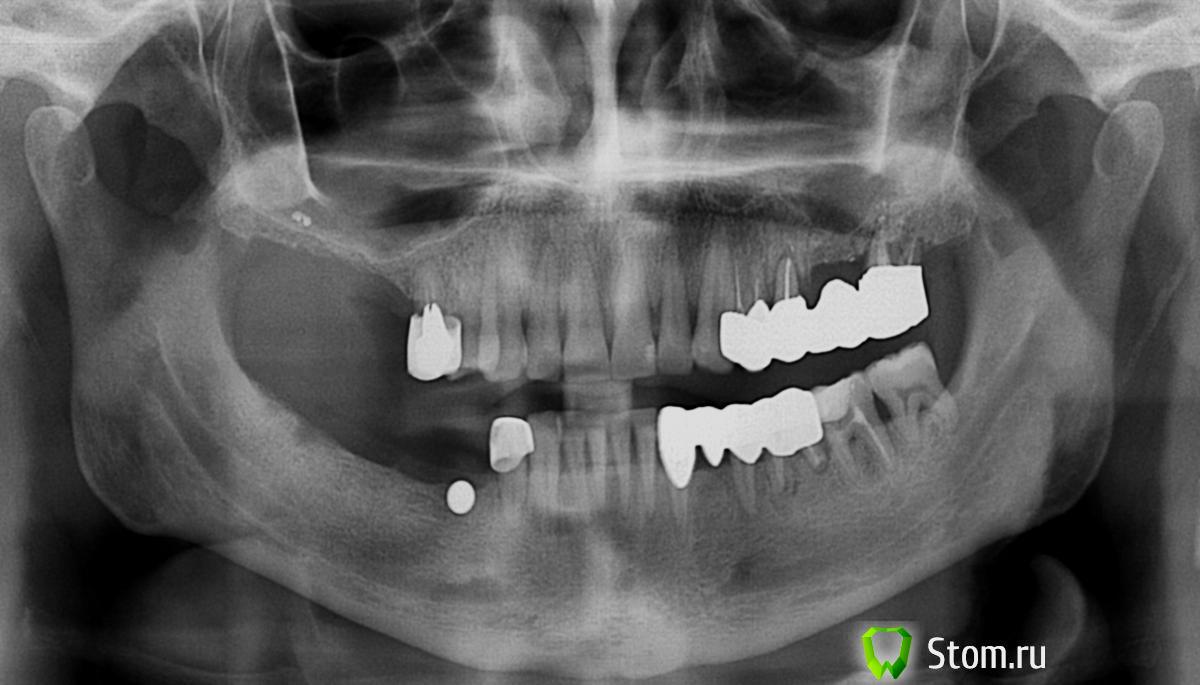

Dr.Politov Опубликовано 24 марта, 2012 Поделиться Опубликовано 24 марта, 2012 Здравствуйте уважаемые коллеги. Очень рад был наткнуться на этот сайт, в частности на форум. Немного о себе: Сам с провинциального города, врач челюстно-лицевой хирург. Пока в начале своего профессионального пути.Выкладываю ОПТГ на первичной консультации (27.12.11г.) и срезы КТ после санации (снятие конструкций, терапевт, пародонтолог) (22.03.12г.). Все удаления выполнялись в середине января. Сейчас этап решения что куда и в какой последовательности. У меня есть план, им я поделюсь ниже, но очень хочется послушать вас, чтобы укрепиться в своём плане или пересмотреть его. Верхняя челюсть:Бюгель, либо двойной синуслифт (после санации левого синуса), через 8 месяцев имплантаты, под несъёмную конструкцию или условно-съёмную.Надеюсь на бюгель согласится ))) Нижняя челюсть:4.5 - 3,75х104.6 - 3,75х104.7 - 4,2х103.4 - 3,75х103.6 - 5.0х10 (но тут вопрос, после удаления прошло 2,5 месяца... ждать или выполнить всё внизу одномоментно и прикрыться Bio-Oss + Bio-Gide? Либо мост на 3.5-3.7 зубы, так как они и так будут покрываться м/к). ps: Он активный курильщик (ещё поэтому я за бюгель на верху) Спасибо, как минимум за внимание ))) Ссылка на комментарий

Bier Опубликовано 25 марта, 2012 Поделиться Опубликовано 25 марта, 2012 зачем вы собираетесь имплантировать 4.7 ?? это лишнее. я против бюгелей, но с пазухой действительно не все хорошо. и еще, если имплантировать 34 и 36 - зачем вам 3.5?? удалили бы его. Ссылка на комментарий

Dr.Politov Опубликовано 28 марта, 2012 Автор Поделиться Опубликовано 28 марта, 2012 зачем вы собираетесь имплантировать 4.7 ?? это лишнее. я против бюгелей, но с пазухой действительно не все хорошо. и еще, если имплантировать 34 и 36 - зачем вам 3.5?? удалили бы его. Спасибо за ответ Bier! Мое изначальное предложение закрыть зубные ряды по шестые. Но у пациента при улыбке видна зона даже седьмых, такой он у нас "большеротик", плюс сама челюсть большая. Так что очень просит седьмые тоже восстановить.По поводу удаления 3.4, после санации, смежными специалистами было решено сохранять, так зуб стабилен.Думаю если имплнтировать 3.6, то получестя карман в дистальной зоне за счет конвергенции 3.7, а удалять 3.7 не целесообразно, так как пациент желает зубной ряд по седьмые. Ссылка на комментарий

Dr.Politov Опубликовано 28 марта, 2012 Автор Поделиться Опубликовано 28 марта, 2012 Спасибо за ответ Bier! Мое изначальное предложение закрыть зубные ряды по шестые. Но у пациента при улыбке видна зона даже седьмых, такой он у нас "большеротик", плюс сама челюсть большая. Так что очень просит седьмые тоже восстановить.По поводу удаления 3.4, после санации, смежными специалистами было решено сохранять, так зуб стабилен.Думаю если имплнтировать 3.6, то получестя карман в дистальной зоне за счет конвергенции 3.7, а удалять 3.7 не целесообразно, так как пациент желает зубной ряд по седьмые. Извиняюсь, не 3.4, а 3.5, опечатка. Ссылка на комментарий

Bier Опубликовано 29 марта, 2012 Поделиться Опубликовано 29 марта, 2012 вы смотрИте не на год вперед. а на больше. 35 не надежный зуб, У него как раз таки будет карман и потеря кости в области соседних имплантатов. А вот 37 зуб вполне нормальный. Поставьте мост на имплантатах 34-36 и забудьте о проблеме на долго. А если смежные специалисты не упускают для "полечить" каждый зубик ))) Ссылка на комментарий

Zborzh Опубликовано 30 марта, 2012 Поделиться Опубликовано 30 марта, 2012 А я бы пообщался с пациентом и оговорил бы план имплантации в области 3.4 , 3.5 , 3.6В области 3.4 слишком кость "слабая",там мало губчатого вещества ... Ссылка на комментарий